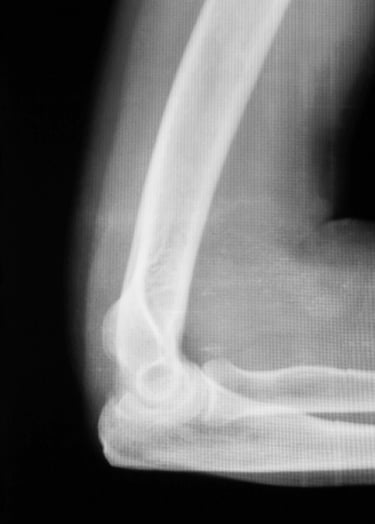

Gydytojas Markas Fiodorovas - ortopedas traumatologas, sporto traumų specialistas, sukaupęs 20 metų patirtį tausojančioje artroskopinėje chirurgijoje. Daugiau nei 650 artroskopinių kelio, peties ir kitų sąnarių operacijų per metus atliekantis chirurgas, taip pat aktyviai įsitraukęs į mokslinę veiklą. Gydytojas yra nuolatinis tarptautinių konferencijų lektorius bei tarptautinis artroskopinės chirurgijos instruktorius.

Gydytojas Markas Fiodorovas - ne tik vienas daugiausiai operuojančių ortopedų - traumatologų Lietuvoje, bet ir aktyvus mokslinės bendruomenės narys, lektorius bei instruktorius. LASTA ir ESKKA asociacijų narys, nuo 2010 metų nuolat skaito pranešimus tarptautinėse konferencijose. Tarptautinis artroskopinės chirurgijos kursų instruktorius nuo 2012m. moko artroskopijos chirurgus visame pasaulyje.